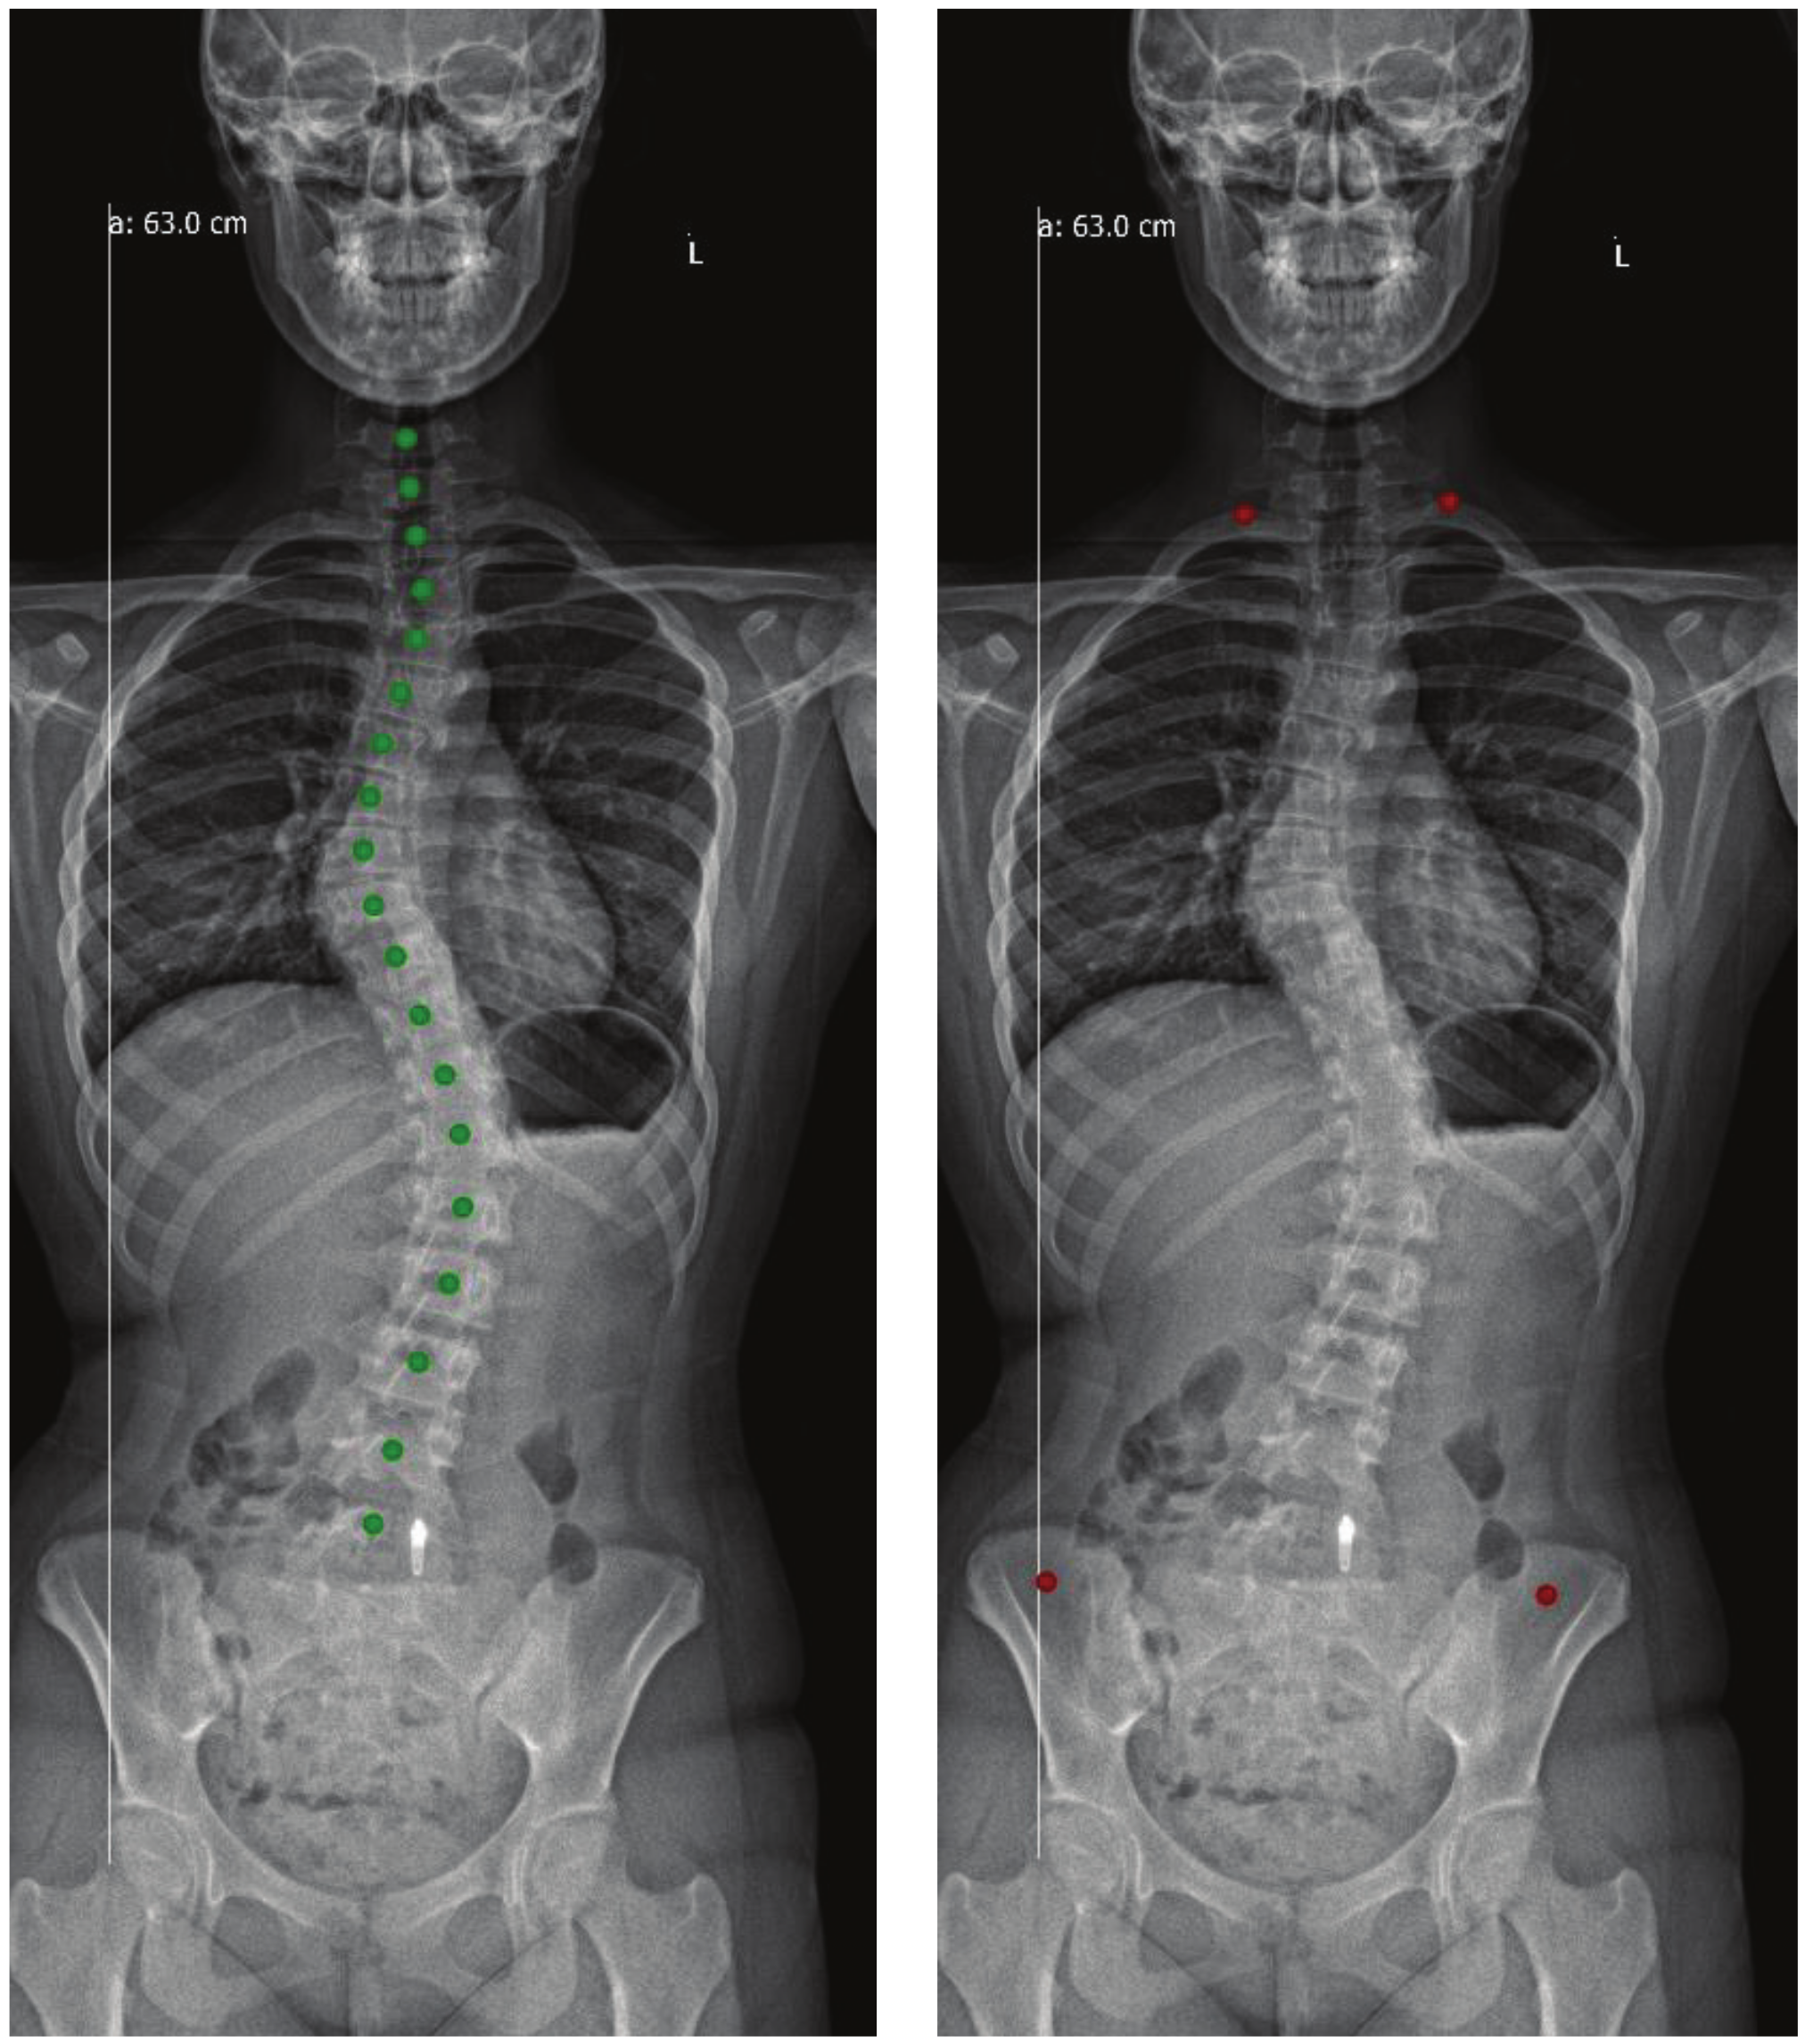

4. Results